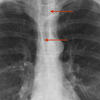

Anterior junction line

Date: 01/11/2010

Views: 5204